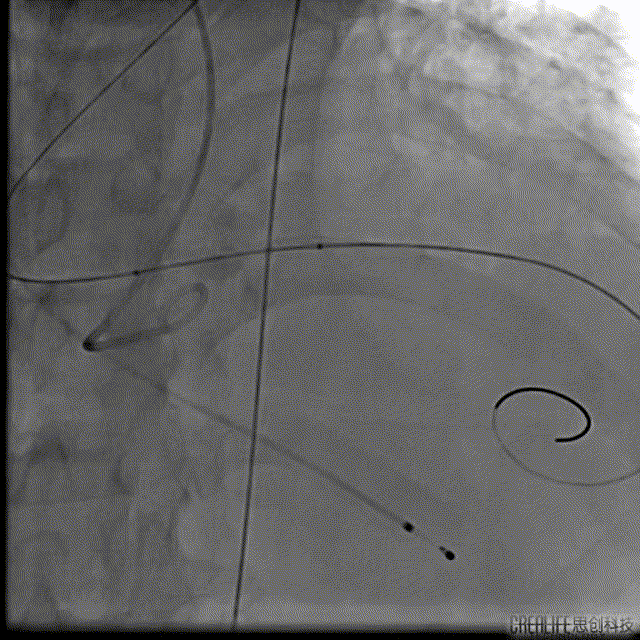

本例患者只有61岁,超声诊断低流速低压差AS,合并升主动脉扩张,CT下测量升主动脉超过50,原则上首选外科手术。但广东省人民医院大血管组会诊后考虑患者低流速低压差,行主动脉瓣和升主动脉置换术,手术风险极高,建议TAVR。从解剖上,瓣环流出道的大小分别是30、31,但瓣上结构是TYPE 0二叶瓣,重度钙化,联合部有钙化融合,瓣上短轴31,窦高度超过23,横位心,角度78°二叶瓣方向呈1点到7点方向。这种解剖做TAVR无疑挑战极大。对于低流速低压差的患者合并解剖挑战的病人,术前计划就是ecmo辅助下TAVR。考虑二叶瓣和重度钙化,目标瓣膜是29号,故用23号球囊预扩,尽量不破坏瓣上结构,另外考虑横位心,升主宽,破裂风险高,瓣膜跨瓣困难,故准备抓捕器辅助跨瓣。投照角度方面准备了瓣膜切线位(左肩),用来跨瓣和球扩,同时准备多一个右足位,这个角度下瓣环和人工瓣膜可以达到共平面,方便瓣膜定位。因为升主宽,横位心,主动脉迂曲,为减少破裂风险,没有选择plus。术中跨瓣遇到较大挑战,因为主动脉根部的角度大,普通的AL2,JR2,多功能导管均无法跨瓣,尝试直头导丝和弯头泥鳅也失败,最后是JL4加直头导丝成功跨瓣。预扩后瓣膜跨瓣尽管在抓捕器辅助下仍然非常困难,在反复尝试后侥幸跨瓣。瓣膜释放后位置偏深,但结合瓣膜角度,瓣周漏可以接受,压差消失,故未再行瓣中瓣。术中未发生停跳,故手术结束后撤去ECMO返回CCU。术后一个月随访EF值明显改善,患者自我感觉明显好转,虽然有中度瓣周漏,但是患者年轻,调整好心功能后,为以后外科置换升主动脉和主动脉瓣打下基础。

VenusA 29瓣膜释放

最后一枪造影

跨瓣压差下降为4mmHg,生命体征平稳,拔出作古ECMO静脉置管后闭合入路,遂送入CCU,术后两天床旁超声显示,人工瓣架功能良好,轻微瓣周漏,术后一个月随访,EF值由21%提升到57%。